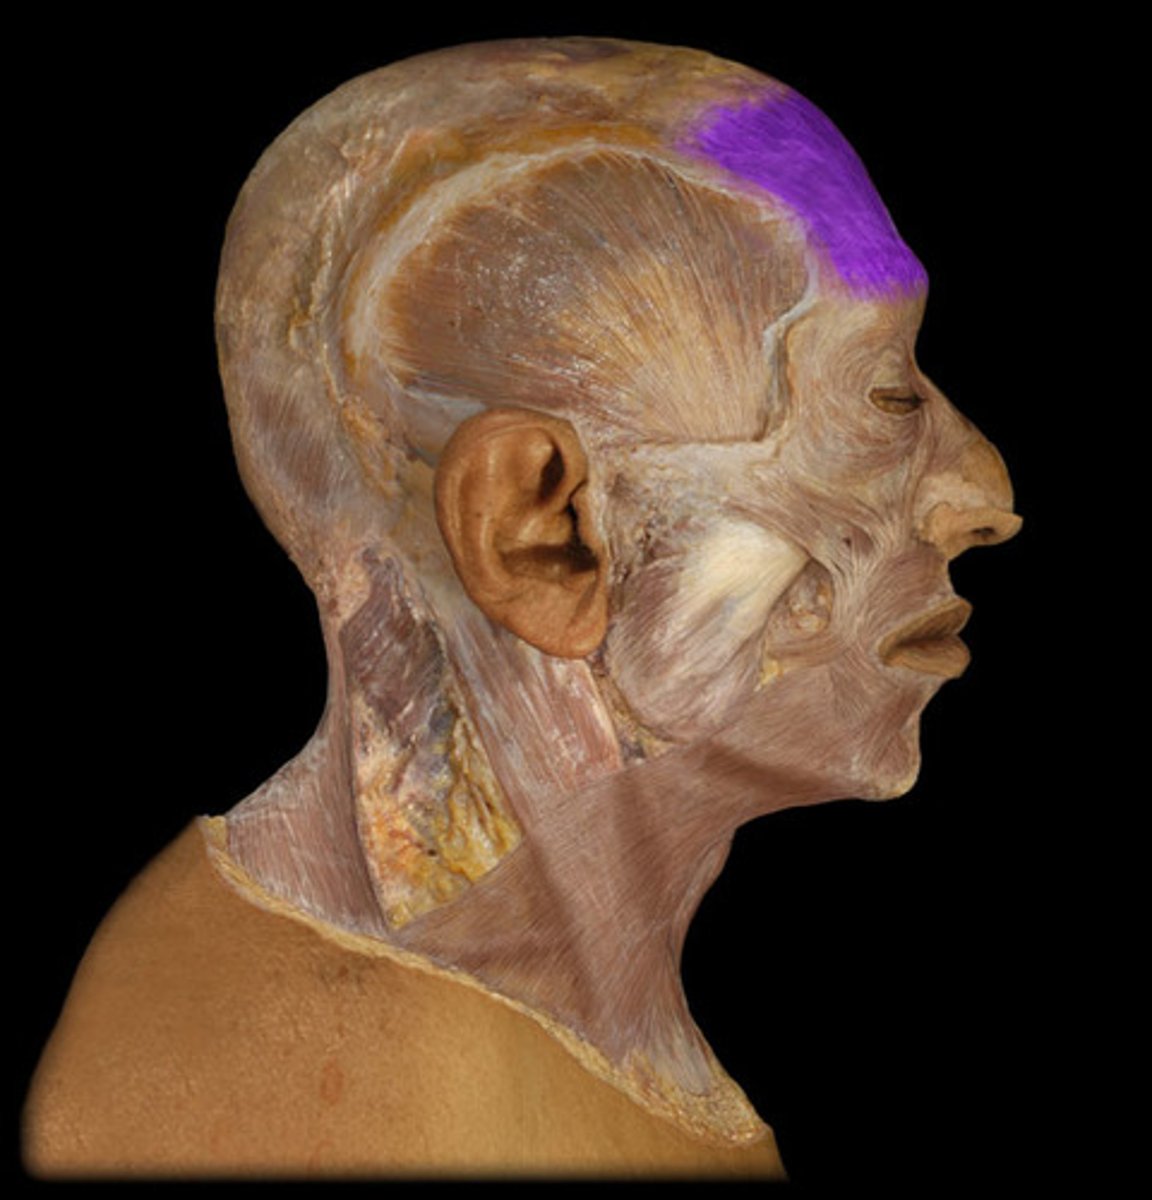

Frontal belly of occipitofrontalis